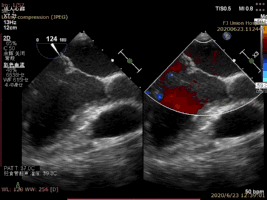

病例1术后二尖瓣反流为轻度